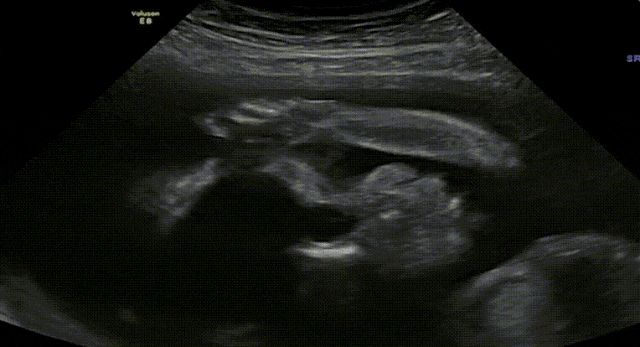

我们单身准妈妈终于迎来了宝宝的喜讯!在我们的帮助下,她找到了心仪的捐赠者,制作出了优质的胚胎。爱妈N特意飞来圣地亚哥的诊所进行移植,一切都进行得非常顺利。今天来诊所进行B超检查,验孕结果成功,虽然宝宝刚刚开始萌芽,但心跳却非常有力,达到了117bpm。我们已经满怀地期待着一个高颜值的混血宝宝的到来了!